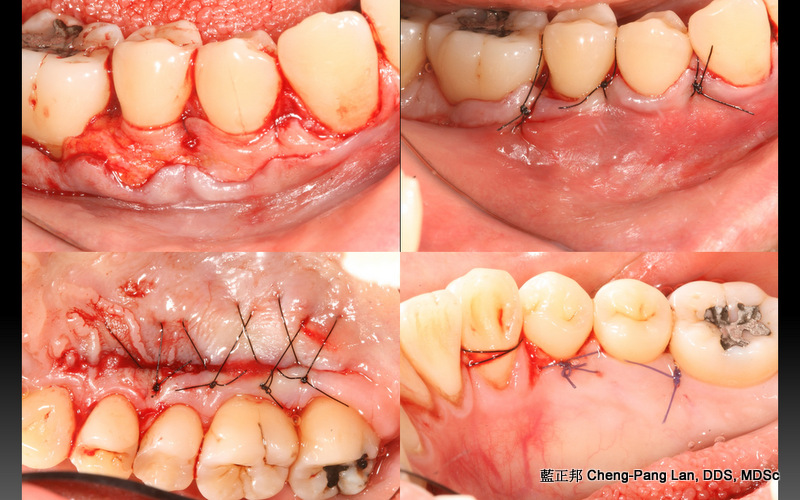

GBR的舌側提升,會讓內側角化組織變少,或是,案例即使沒補骨,原本就舌側角化組織缺乏。這幾年自己也想解決這個難題。試了幾個不同做法,有一些心得。

一開始的Partial Thickness皮瓣移動,只須刀片劃開表層,其餘用鈍器械推下去。跟Tension free flap release這篇的手法類似。意即,切得少,推得多。

固定的關鍵,這幾年我發現,是縫針。因為有舌頭會移動,空間小,不易操作,而且進針、取針時機很短。縫針找1/2彎度,短如10mm,短進短出,要快,沒有多餘時間再找針頭。針還要利,故角針遠比圓針更好。個人經驗,縫針規格,3/8 彎度,13mm以上,也可以,但是會增加手術難度。短、勾、銳,很重要。

還有另一個固定的技巧。一開始graft容易滑動,用針進出graft,不容易固定。不如專注在cross mattress進出旁邊的骨膜上,利用縫線先將graft壓住。縫到尾聲再用針進出graft,做最後固定。